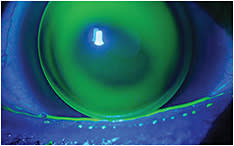

With keratoconus as an example, coding for the patient’s experience

- 92072. This code is used for the fitting of a contact lens for the management of keratoconus.

- 92025. Computerized corneal topography, unilateral or bilateral, with interpretation and report. Code 92025 is defined as “unilateral or bilateral,” so reimbursement is the same whether one or both eyes are tested.